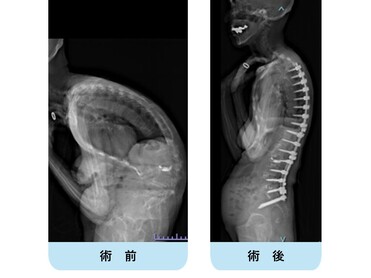

高度腰曲がり・脊柱後弯症・成人脊柱変形の患者さんです。難治性の腰痛、バランス不良により歩くことも困難な状態でした。

腰椎側方経路椎体間固定術と後方矯正固定術を2回に分けて行い、生理的な胸椎後弯・腰仙椎前弯・骨盤前傾が復元されました。腰痛・歩行障害は改善し、近所のスーパーへ歩いて買い物にも行けるようになり、台所の仕事も痛みなく出来るようになりました。